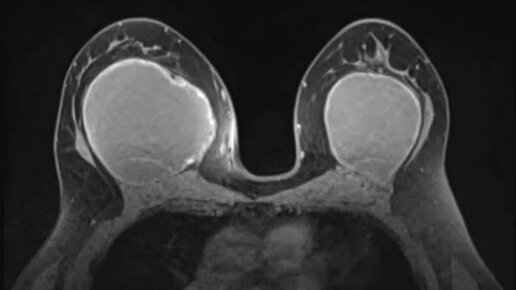

Гелеомы

Маммология и хирургия РНЦРР